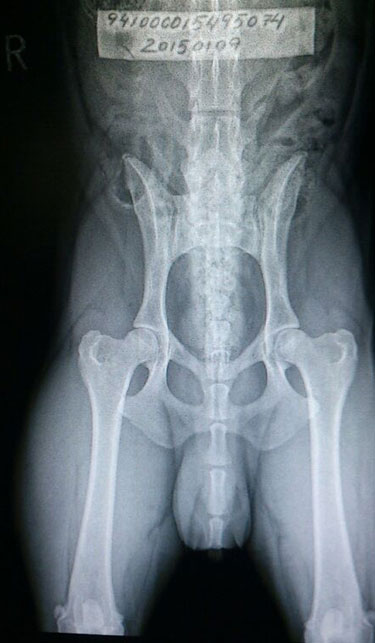

X-On